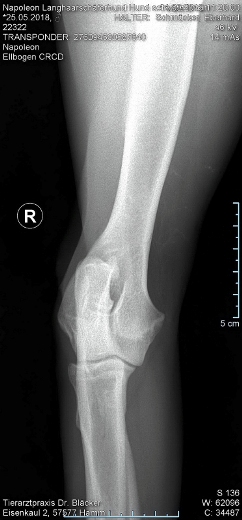

Keine HD  und  kein ED

Röntgentermin am 11.09.2019

Hier sind  HD-ED Aufnahmen von unseren “Napoleon von KaTum”   alles Top

Keine HD und kein ED,LÜW ist alles gut